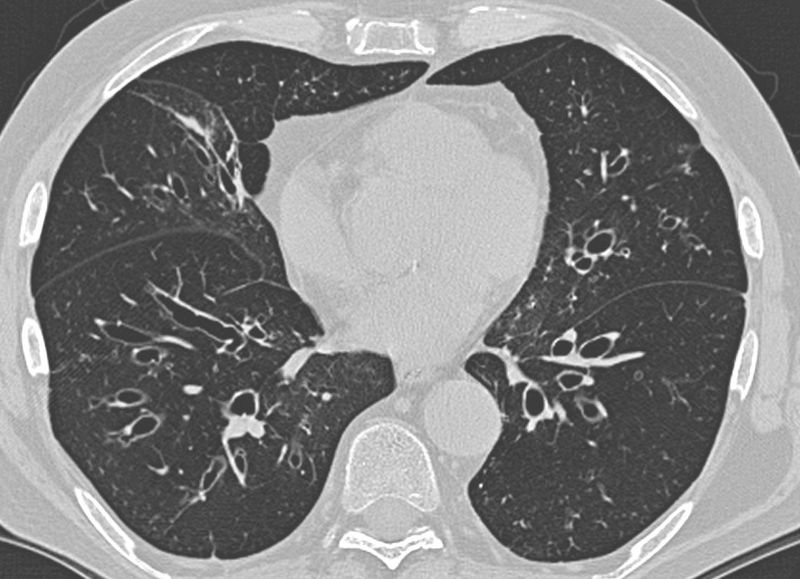

Register for our upcoming @EuroRespSoc webinar on implementing the new ERS bronchiectasis guidelines - a practical session with PJ McShane, @MichalShteinbe1 Charlie Haworth, @AlibertiStefano and Melissa McDonnell